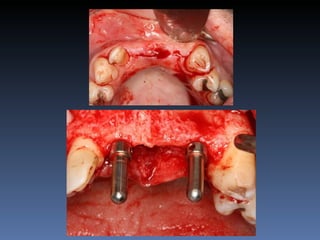

BOX 3

Diagnóstico: Desdentado parcial

bilateral posterior da mandíbula.

Plano de tratamento: Reabilitação bilateral posterior

mandibular com instalação de 6 implantes endo-

ósseos, para reabilitação protética fixa.

Zona 4.4, 4.5, 4.6   Zona 3.5, 3.6, 3.7